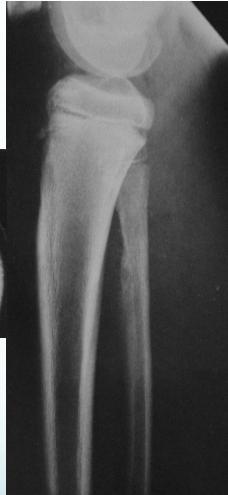

Radiological Features

- X-ray:

- Diaphyseal

- Bone destruction

- New bone formation:

- Along the bone

- “Onion-peel” layers

- ? “Sun-ray”

- ? Codman’s triangle

- Secondaries – in skeleton

Source: Apley’s System of Orthop. And Fractures